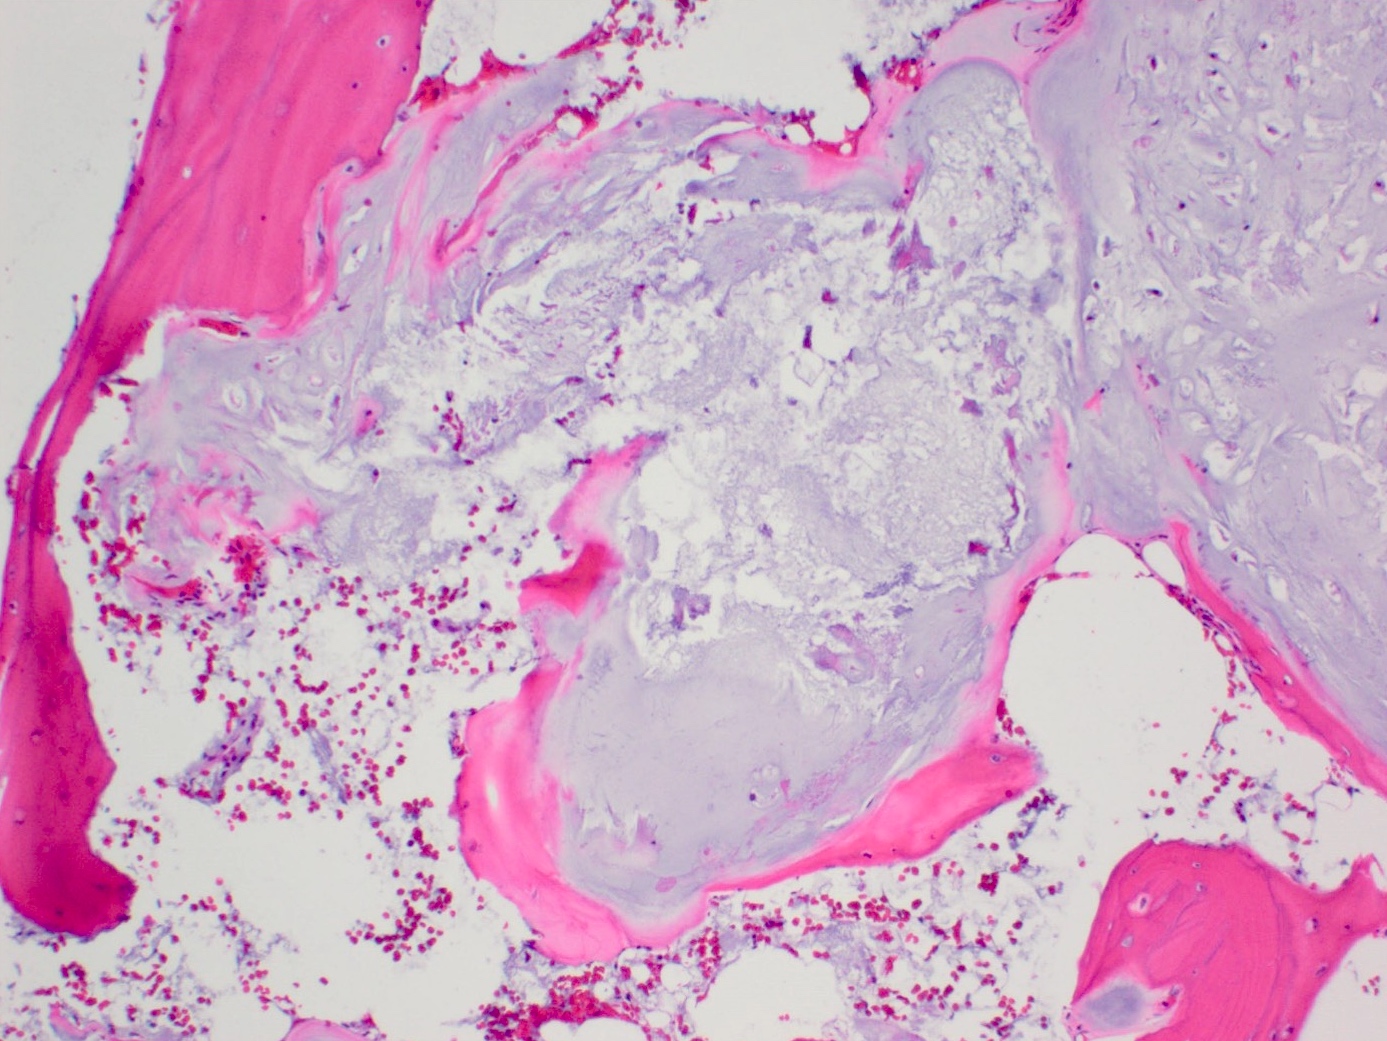

Microscopic (histologic) description

- Lobulated growth pattern (J Dent Res Dent Clin Dent Prospects 2011;5:98)

- Lobules have irregular shapes and sizes and may be separated by fibrous bands containing small vessels (Virchows Arch 2012;460:95)

- Lobules are composed of abundant hyaline cartilage matrix (sometimes with mucoid / myxoid changes) and permeate and entrap lamellar bone trabeculae

- Cellularity is slightly higher than in enchondroma

- Cells show moderate eosinophilic to vacuolated cytoplasm

- Nuclei are small and uniform with condensed chromatin (lymphocyte-like); sometimes they show open chromatin with visible nucleoli (Am J Surg Pathol 2009;33:50)

- Mitoses and significant nuclear pleomorphism are absent

- Binucleation can be observed

- Necrosis can be seen

- In cases arising from pre-existing enchondromas, areas of enchondroma with calcifications can be present

- In cases arising from pre-existing osteochondroma, evidence of this tumor can be seen (Mod Pathol 2012;25:1275)

Microscopic (histologic) images

- Bone, left 5th and 4th metatarsals, excision:

- Atypical cartilaginous tumor (see microscopic description)

- Microscopic description: Examination of the histopathologic sections reveals mature trabecular bone with juxtaposed cartilaginous proliferation, characterized by low to moderate cellularity, chondrocytes with occasional binucleated cells and mild atypia in a hyaline cartilage matrix. Foci of necrosis, nonischemic type are seen. Given the presence of nonischemic type necrosis, the large size of the tumor and the cellular atypia, the tumor is most consistent with atypical cartilaginous tumor that may have arisen from an osteochondroma.

Practice question #1

A 41 year old woman complained of an enlarging mass at her left proximal humerus. Xrays showed a lucent lesion with indistinct borders and endosteal scalloping. MRI showed an irregular, expansile, avidly enhancing mass. A biopsy of the lesion was performed and is shown above. What is the diagnosis?